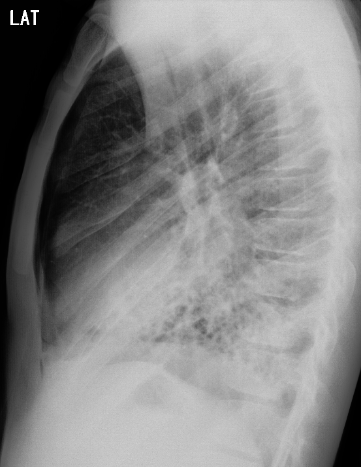

Foi solicitada radiografia do tórax em AP e perfil.

Diante das imagens, qual achado pode ser responsável pela piora súbita na dispneia?

BPequeno pneumotórax à direita

DPneumonia em base direita